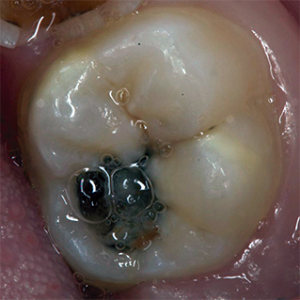

Encontramos el órgano dental 46 con una cavidad bastante profunda que nos reflejó una lesión amplia con una hipomineralización franca con actividad cariogénica. (Figura 1).